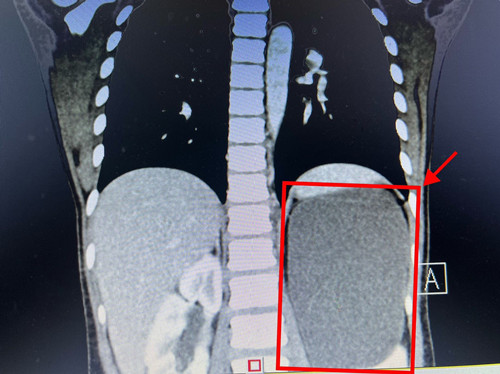

“孩子以前没有特别的症状,所以根本没想到会有一个这么大的瘤子。”小菲的家人介绍。经过检查,畸胎瘤位于小菲的腹腔内左侧,最长处直径有15厘米,盘踞在腹腔诸多重要脏器和血管之间,需手术切除。

考虑到瘤体主要位于胰头后方、腹主动脉前方,上方毗邻肝脏,下方是脾静脉及脾脏,不仅挤压了右侧的门静脉和下腔静脉,连肾上极也被挤压。这些都是维持人体生命的重要大血管及脏器,手术中伤及任何一处都有可能导致大出血,危及生命。儿童血液肿瘤科贺湘玲接诊小菲后,联合医院实体肿瘤MDT团队对小菲的情况进行讨论。儿童外科主任阎大益组织血液肿瘤科、泌尿外科、肝胆外科、麻醉科等多学科会诊,对小菲进行全面综合评估,对术中可能出现的问题及处置预案展开了详细的讨论,并制定了周详的手术计划。